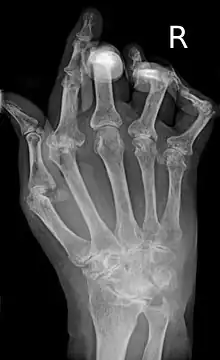

A hand severely affected by rheumatoid arthritis. This degree of swelling and deformation does not typically occur with current treatment.